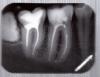

Didi Опубликовано 16 ноября, 2009 Поделиться Опубликовано 16 ноября, 2009 (изменено) Здравствуйте, скажите пожалуйста глядя на этот снимокhttp://piccy.info/ru/view/7c13ef3253b002df...c7427/original/Насколько мудро будет перепломбировать каналы во всех этих зубах если они запломбированы пастой ФОРЕДЕНТ (на основе резорцина-формальдегида)? Насколько сложна распломбировка маляров если с момента пломбировки прошло два с половиной года? Вреден ли формальдегид когда он выходит за апикальную полость или же когда он заканчивается у устья тоже по организму может распространятся? Какое его количество теоретически попадает в организм в граммах в данной ситуации? Продолжается ли его распространение спустя время или он выходит постепенно, а в апикальной полость (над каналом) его уже не содержится? И ещё, правда ли то что пасты на основе резорцина-формалина увеличивают хрупкость зуба, настолько что потом его нельзя использовать как опору? (читал в одной статейке) Просьба каждому написать своё мнение и рекомендацию относительно вопроса... Изменено 16 ноября, 2009 пользователем Didi Ссылка на комментарий

Fred Опубликовано 16 ноября, 2009 Поделиться Опубликовано 16 ноября, 2009 Здравствуйте, скажите пожалуйста глядя на этот снимокhttp://piccy.info/ru/view/7c13ef3253b002df...c7427/original/Насколько мудро будет перепломбировать каналы во всех этих зубах если они запломбированы пастой ФОРЕДЕНТ (на основе резорцина-формальдегида)? Насколько сложна распломбировка маляров если с момента пломбировки прошло два с половиной года? Вреден ли формальдегид когда он выходит за апикальную полость или же когда он заканчивается у устья тоже по организму может распространятся? Какое его количество теоретически попадает в организм в граммах в данной ситуации? Продолжается ли его распространение спустя время или он выходит постепенно, а в апикальной полость (над каналом) его уже не содержится? И ещё, правда ли то что пасты на основе резорцина-формалина увеличивают хрупкость зуба, настолько что потом его нельзя использовать как опору? (читал в одной статейке)Просьба каждому написать своё мнение и рекомендацию относительно вопроса... К сожалению, по панорамке оценить все зубы достаточно сложно, но одноканальные зубы пломбированы вполне адекватно. Нужно было бы видеть не только фотографию, но и оценить консистенцию вещества воочию. Формальдегид (ФА), к сожалению, вреден, выходит он постоянно, но в очень малых количествах. Я когда-то считал, что всего в зуб может поместиться около 10-20 мг любого вещества. Вот представьте, даже если это все вещество было бы ФА, то это был бы теоретический максимум выделения за всю жизнь. Выделяется ФА из затвердевшего материала где-то около нескольки процентов, да и далеко не весь канал забит только ФА выделяющим веществом, там немало добавок есть ... Получается около десятков микрограмм за всю жизнь. Для сравнения, с одной сигаретой, чашкой кофе, банкой пива или кока-колы получаете около миллиграмма. Говорят, что зуб становится более хрупким, по-моему, это субъективные наблюдения, во всяком случае, исследований я не знаю. Как опору использовать зуб можно, если он еще пригоден для протезирования. Фотографии верхних моляров хотелось бы получить на "маленьких" снимках. Ссылка на комментарий

Didi Опубликовано 19 ноября, 2009 Автор Поделиться Опубликовано 19 ноября, 2009 Здравствуйте, вот снимкиЭтот был сделан весной примерно: А эти сегодня:http://i.piccy.info/i4/a0/2d/ca422fdae050973dbb800b1a2bae.jpeghttp://i.piccy.info/i4/90/fd/2d91053ef2069f9c2d834fc3d3d8.jpegСудя по снимку 7-ки, можно ли считать что материал в канале рассасывается? Мой Вам совет, про свойства материалов спрашивайте у химиков, биохимиков, фармакологов, но никак не у стоматологов. Последние в этом ничего не смыслят.Жалко, но мне всё же интересно что бы они порекомендовали делать с зубами запломбированым этой пастой к красяще-рассасывающимися свойствами Ссылка на комментарий

Fred Опубликовано 19 ноября, 2009 Поделиться Опубликовано 19 ноября, 2009 Здравствуйте, вот снимкиЭтот был сделан весной примерно: Судя по снимку 7-ки, можно ли считать что материал в канале рассасывается?Жалко, но мне всё же интересно что бы они порекомендовали делать с зубами запломбированым этой пастой к красяще-рассасывающимися свойствами Сначала просто спрошу, какие из зубов планируют протезировать?Если снимки покажете типичному эндодонтологу, гарантия, что будет "перелечивать" или пробовать "перелечить" все. Особенно после того, как узнает, что там резорцинформалин. И еще, скажите, когда который из этих зубов пломбирован, и были ли когда-н боли, флюсы у этих зубов после последней пломбировки каналов? Ссылка на комментарий